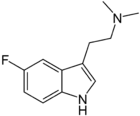

| 5-Fluoro-DMT | artificial | 5-F | CH3 | CH3 | 5-fluoro-N,N-dimethyltryptamine | 22120-36-1 |